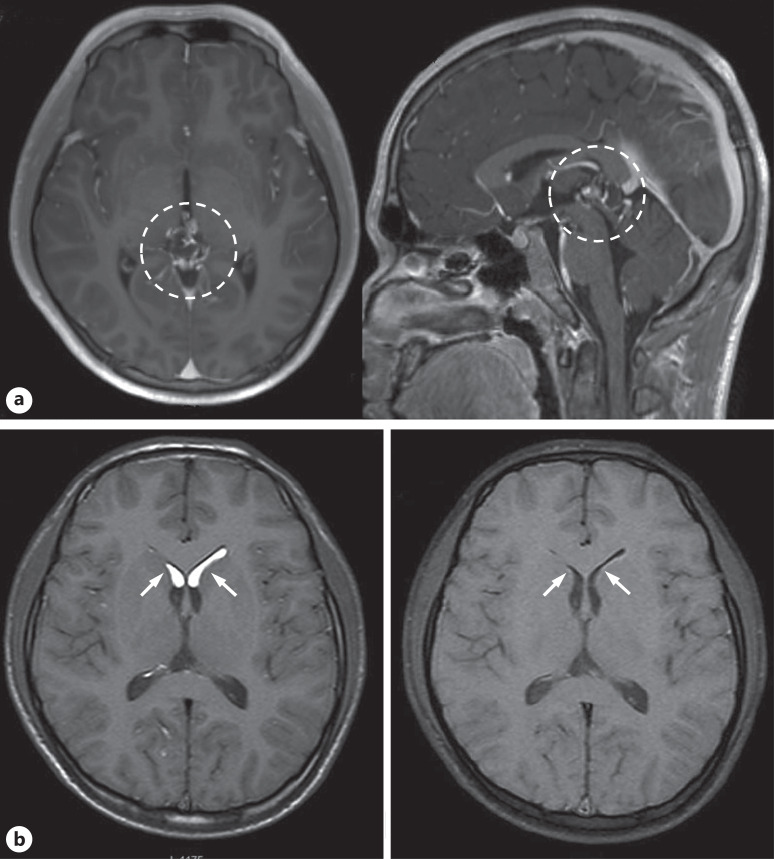

Case presentation: A 15-year-old boy presented with a 2-month history of persistent headaches. Computed tomography revealed a calcified mass lesion in the pineal region with low-density areas in the lateral ventricles. Magnetic resonance imaging (MRI) demonstrated a complex lesion in the pineal region and high T1 signal intensity bilaterally in the anterior horns of the lateral ventricles, suggestive of a ruptured teratoma. The patient underwent surgical resection. Postoperatively, he developed mild fever, severe headache, ocular pain, decreased vision, diplopia, and neck rigidity. Contrast-enhanced MRI revealed faint meningeal enhancement, consistent with aseptic meningitis. Symptoms gradually improved with steroid therapy.